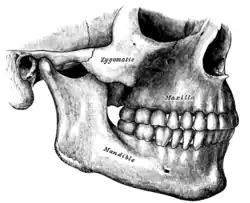

Osso zigomático esquerdo. Superfície de Malar.

Osso zigomático esquerdo. Superfície de Malar. Osso zigomático esquerdo. Superfície temporal.

Osso zigomático esquerdo. Superfície temporal. Visão lateral do crânio.

Visão lateral do crânio. Fossa infratemporal esquerda.